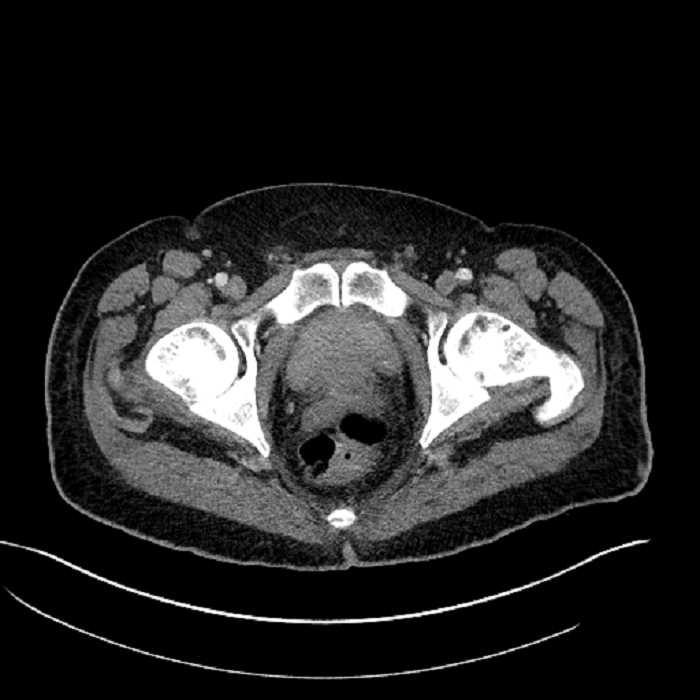

Age: 63

Sex: Male

Indication: Abdominal pain

• High grade stenosis of the left common iliac artery, with the left internal and external iliac arteries remaining patent

• Ankylosis of both sacroiliac joints

Acute sigmoid diverticulitis complicated by a small contained perforation and a large abscess in the right hepatic lobe. Additional small subcapsular abscesses along the anterior margin of the left hepatic lobe.

High grade stenosis of the left common iliac artery. The left external and internal iliac arteries are patent.

Hepatic abscess showing the double target sign with low density internally surrounded by a thin inner enhancing rim (red arrow) and ill-defined outer low density rim (yellow arrow). Blue arrow indicates an internal septation. Red arrows: additional smaller subcapsular abscesses. Red arrow: focal contained perforation associated with diverticulitis.